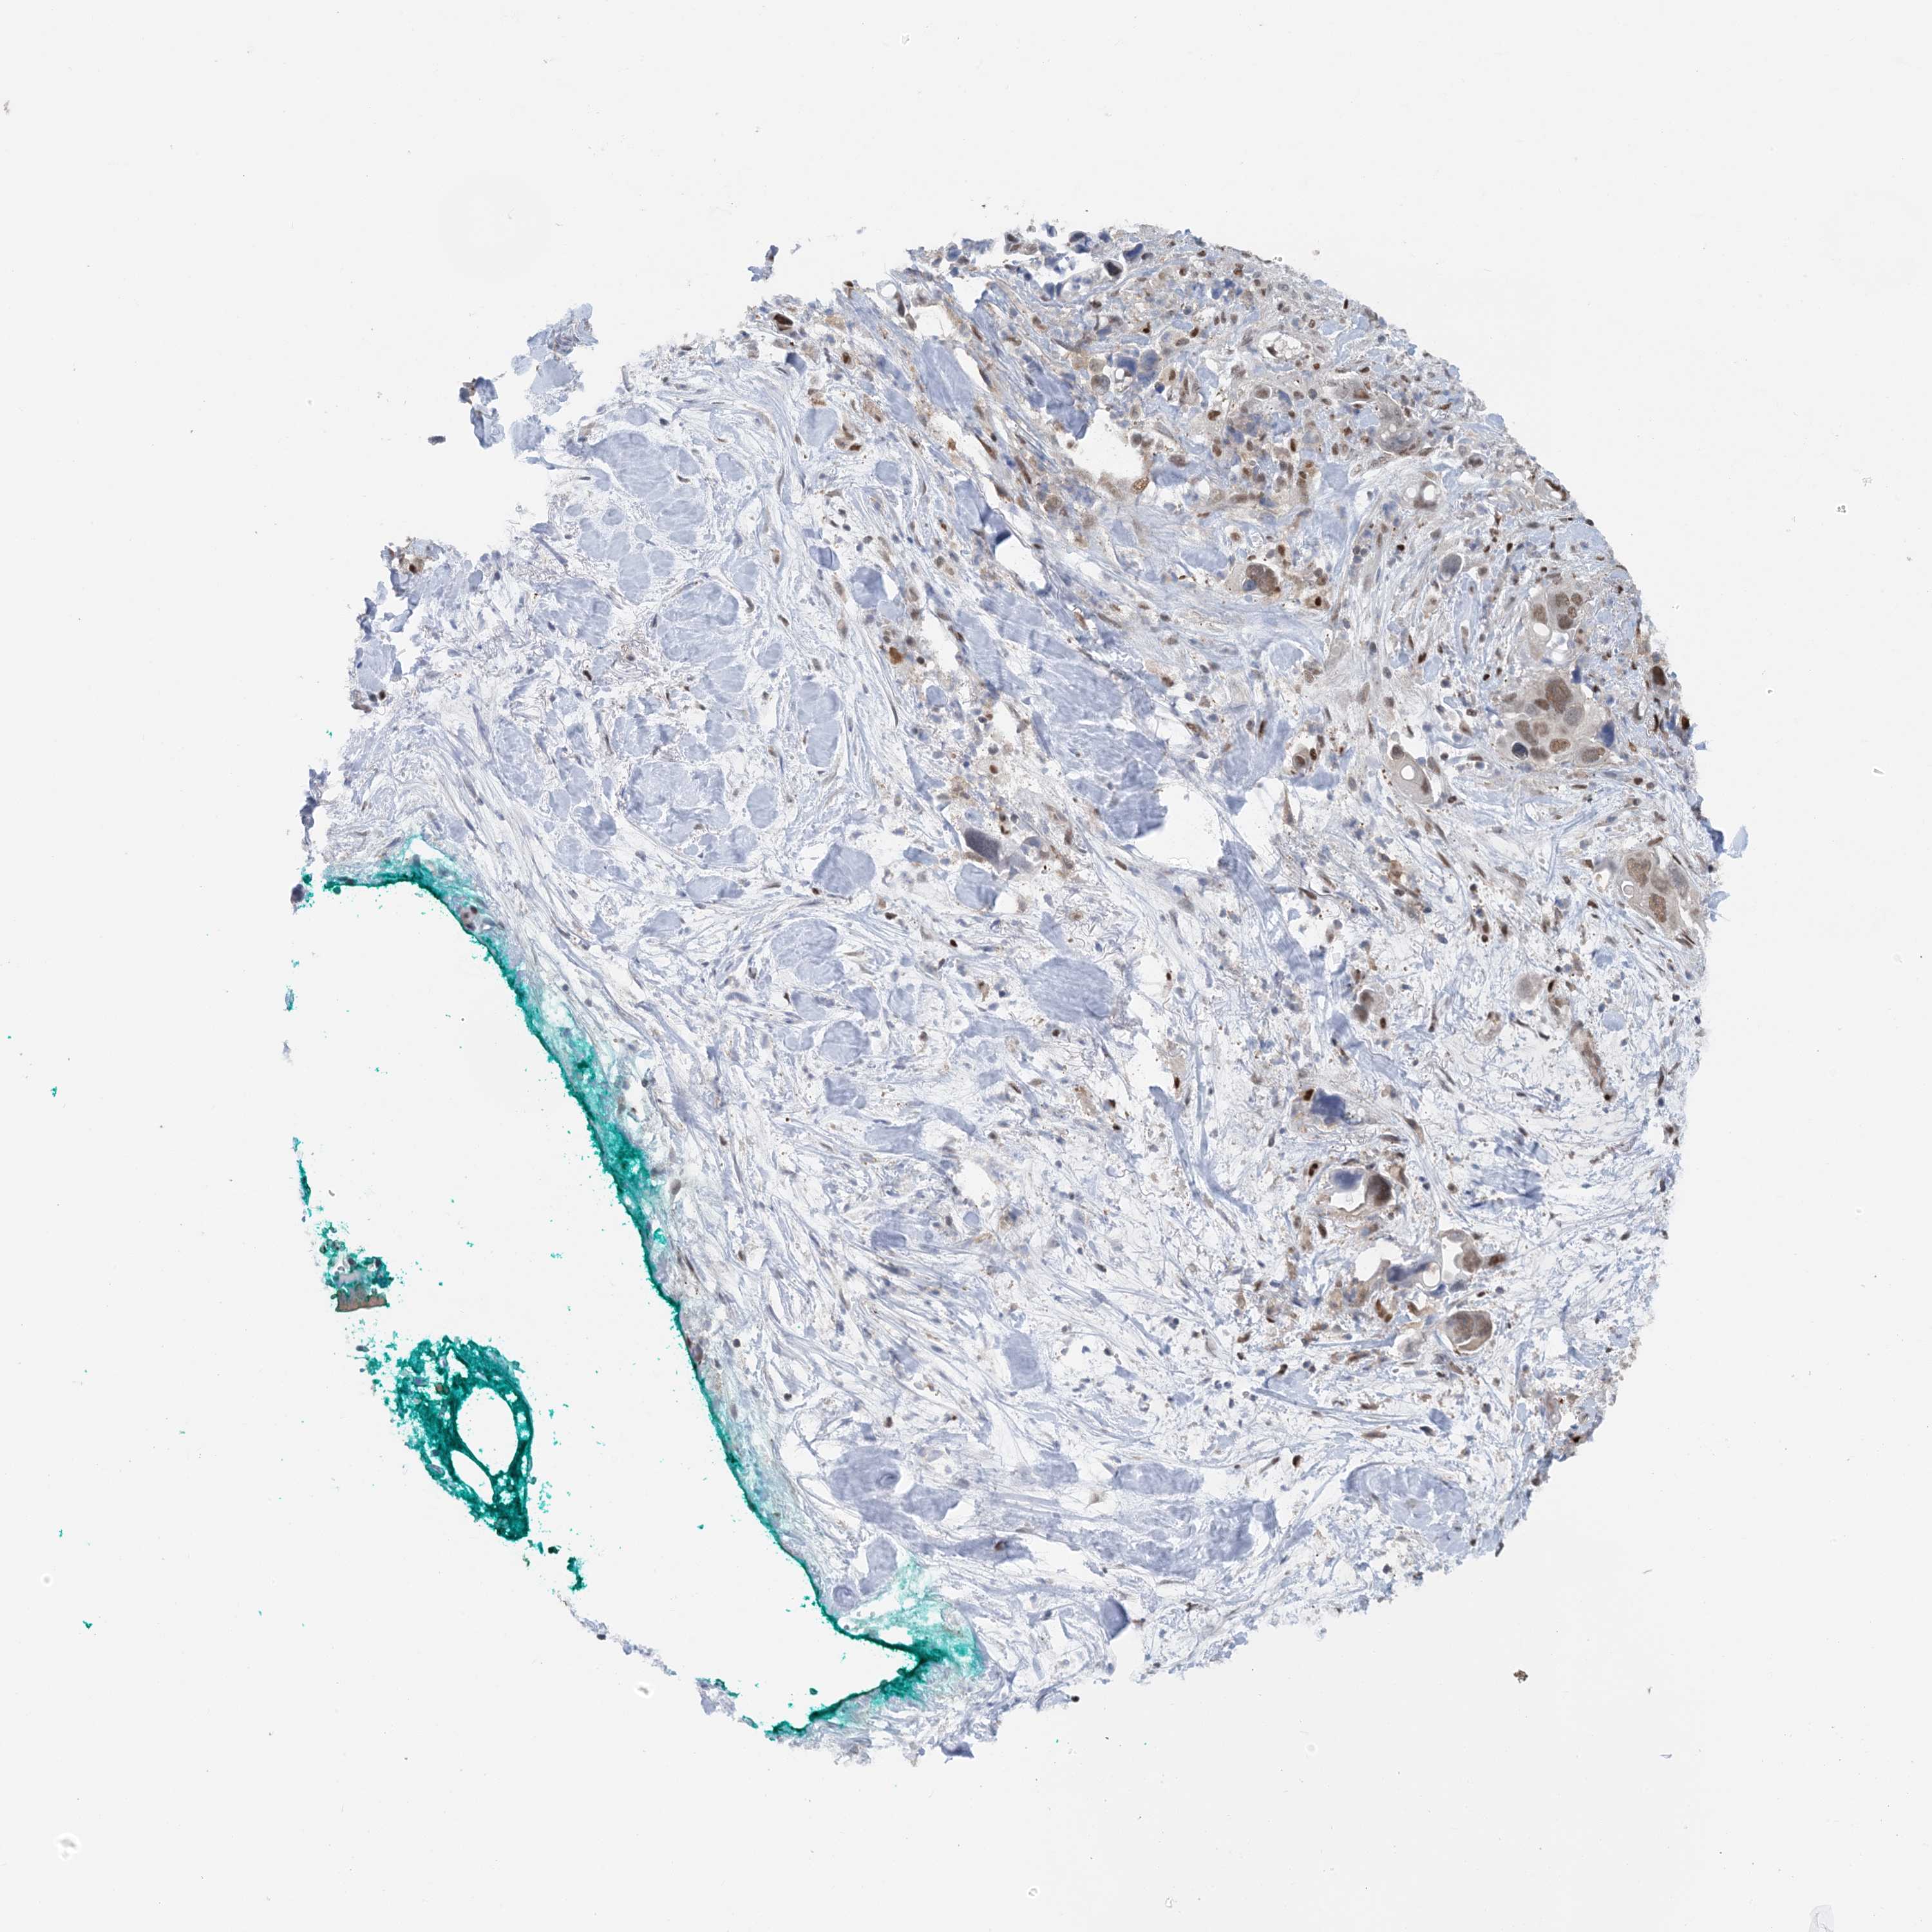

PANCREATIC CANCER - Protein expressioni

A mouse-over function shows sample information and annotation data. Click on an image to view it in a full screen mode. Samples can be filtered based on level of antibody staining by selecting one or several of the following categories: high, medium, low and not detected. The assay and annotation is described here.

Note that samples used for immunohistochemistry by the Human Protein Atlas do not correspond to samples in the TCGA dataset.

Antibody stainingi

Antibody staining in the annotated cell types in the current human tissue is reported as not detected, low, medium, or high, based on conventional immunohistochemistry profiling in selected tissues. This score is based on the combination of the staining intensity and fraction of stained cells.

Each image is clickable and will lead to virtual microscopy that enables deeper exploration of all samples and also displays staining intensity scores, fraction scores and subcellular localization as well as patient and tissue information for each sample.

Antibody HPA035063

Antibody HPA035064

Staining

High

Medium

Low

Not detected

Intensity

Strong

Moderate

Weak

Negative

Quantity

>75%

75%-25%

<25%

None

Location

Nuclear

Cytoplasmic/membranous

Cytoplasmic/membranous,nuclear

Adenocarcinoma, NOS